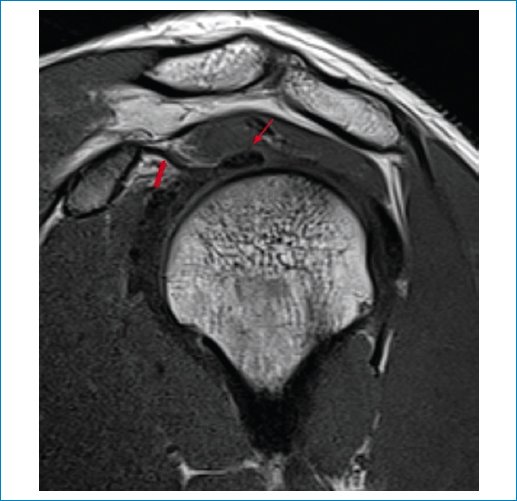

En nuestra serie aplicamos los criterios de Emig et al.11, que incluyen la hiperintensidad o el engrosamiento del ligamento glenohumeral inferior > 3 mm (Figs. 1 a 3), el engrosamiento capsular del receso axilar (con valores que varían según los estudios, pero descrito en general como > 7 mm) (Fig. 3), el engrosamiento del ligamento coracohumeral > 4 mm (Fig. 4), la infiltración grasa y la hiperintensidad del intervalo rotador (Figs. 5 a 7), y la obliteración de la grasa subcoracoidea (descrita como ausente, parcial o completa) (Fig. 8).

Figura 1. RM en secuencia DP-FS, corte coronal. Se observa un engrosamiento del ligamento glenohumeral inferior con señal hiperintensa en el receso axilar (flecha).

Figura 3. RM en secuencia DP-FS, corte coronal. Se observan el engrosamiento capsular y la medida de la altura y el ancho máximos de la bolsa axilar (flechas).